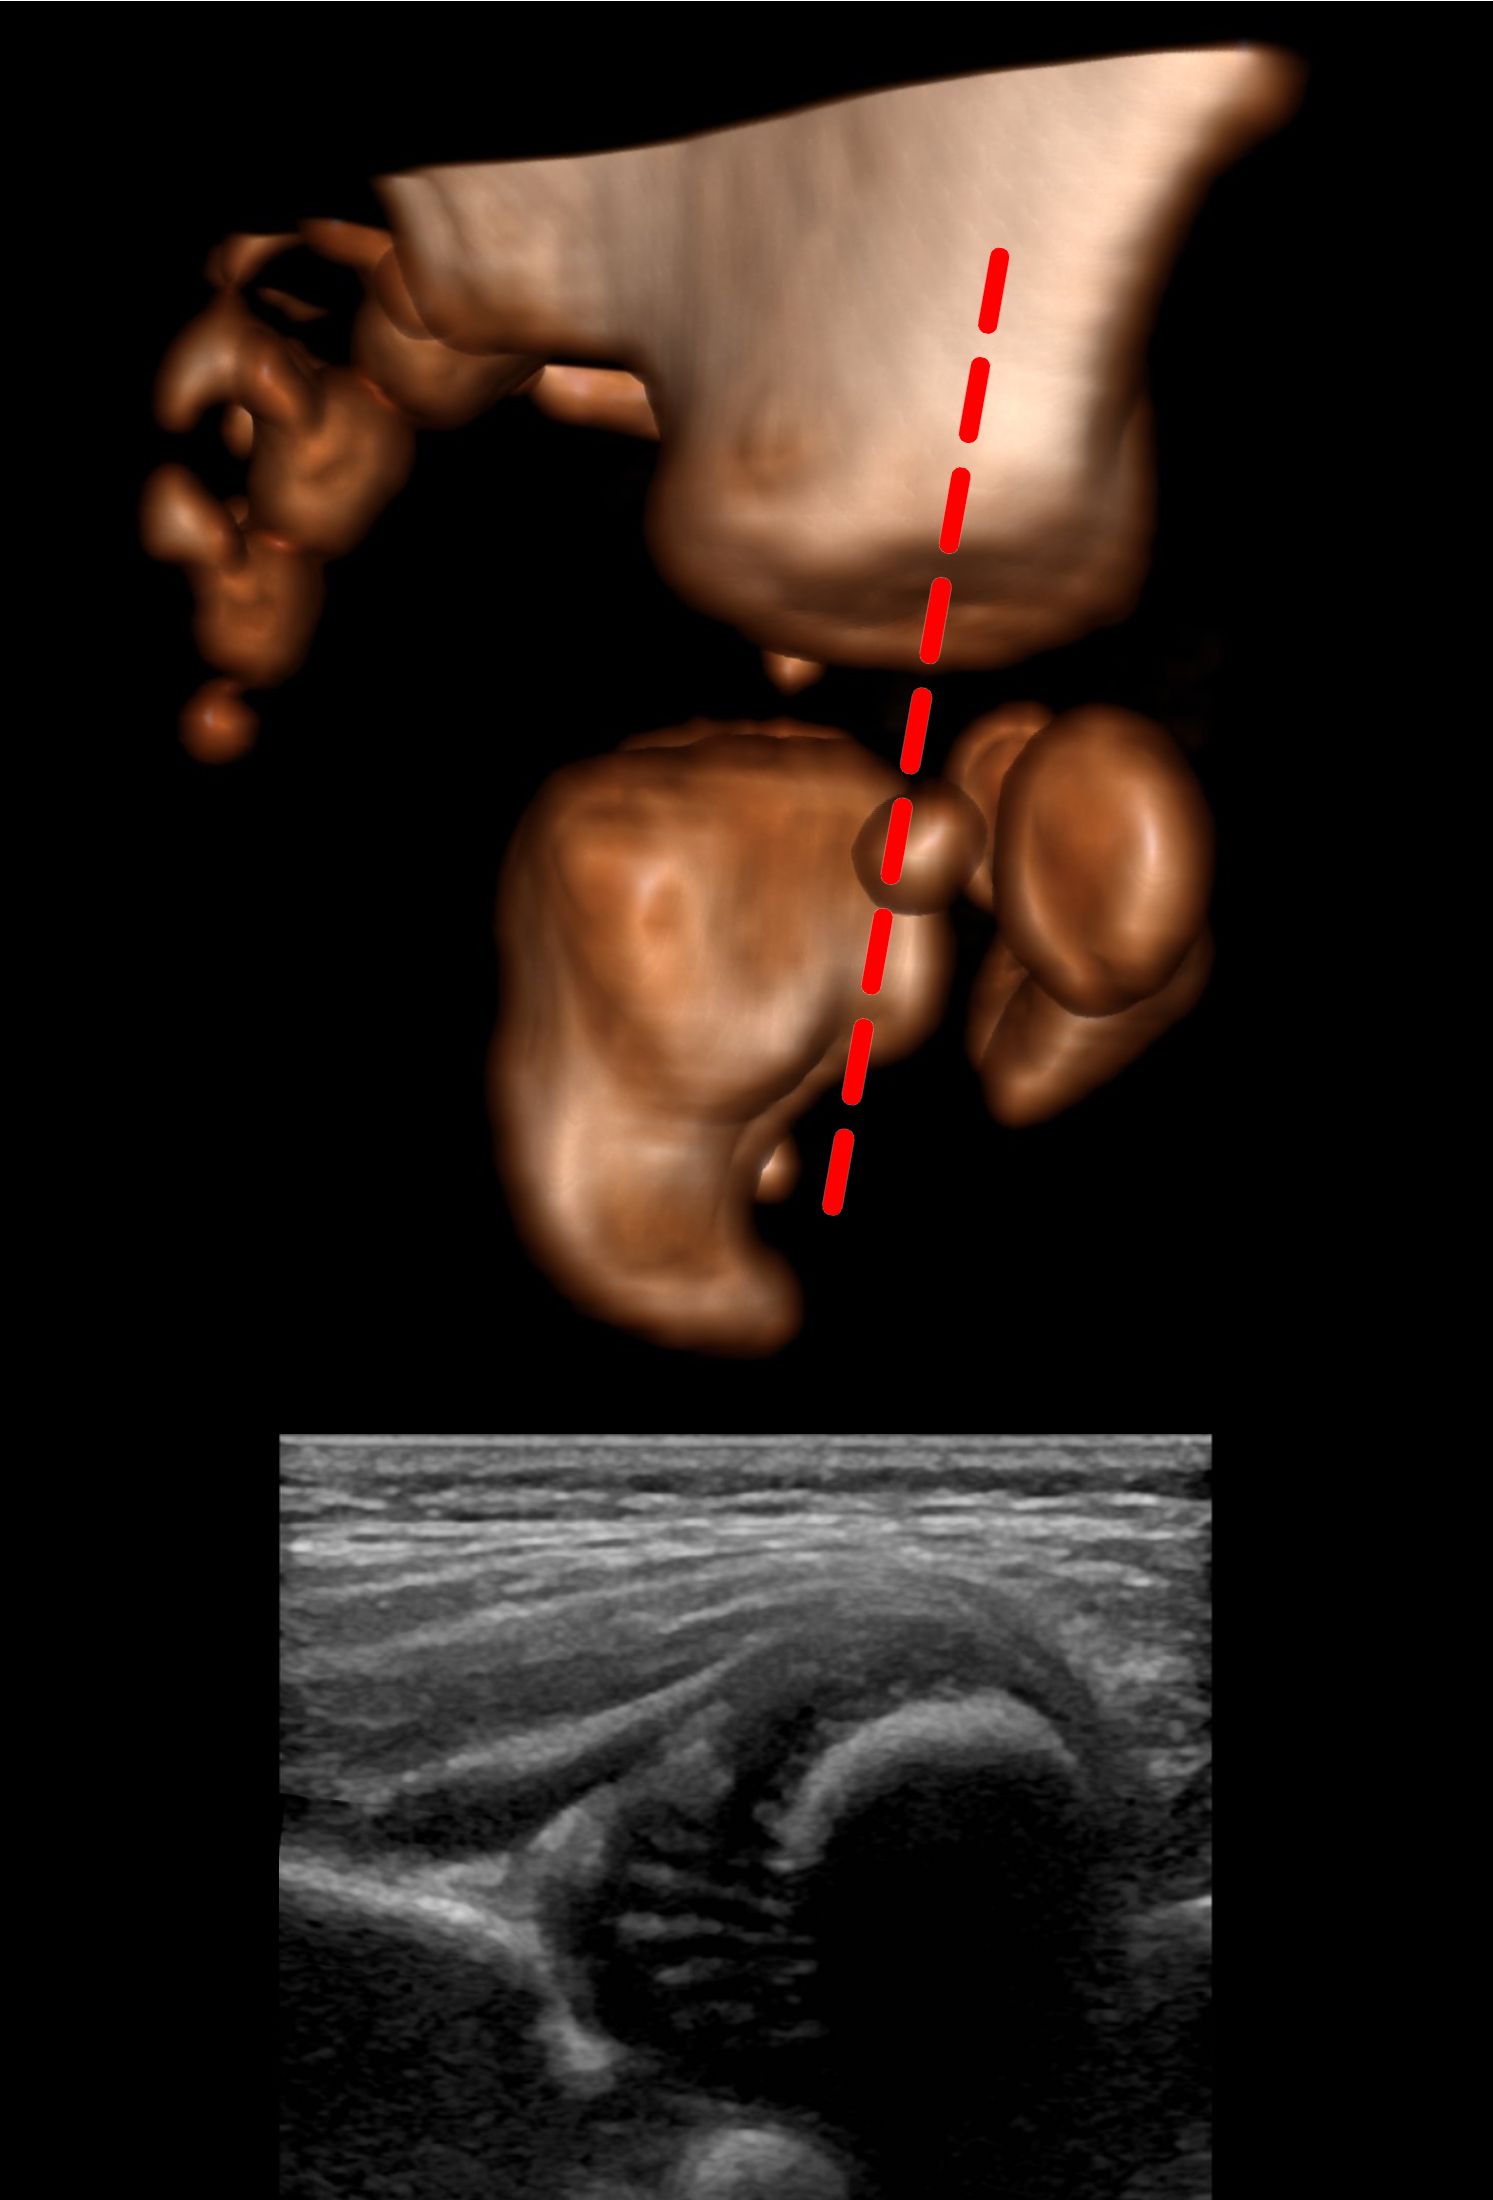

Using the Graf method the hips should be slightly flexed [1, 2]. The patient should be on their side and the probe is placed, vertically orientated, on the lateral aspect of the hip.

After identifying the osteochondral junction, the femoral head, synovial fold, joint capsule, acetabular labrum, acetabular cartilage, bony roof of the acetabulum and turning point (see earlier) should be identified. The lower limb of the ilium and the triradiate cartilage indicate the acetabular center. The ilium should then be made straight on the screen. Since, at this point, the ilium raises anteriorly and superiorly and falls posteriorly and inferiorly, to get a straight image of the ilium, you need to align the probe between the rise and the fall.

And if you rotate anticlockwise, it will cause it to fall as a curve:

So to make a straight line you either chase it down by rotating anticlockwise or raise it up by rotating clockwise whilst maintaining the centre of rotation such that the structures of interest remain on screen. The opposite rotation is needed when scanning the left hip.